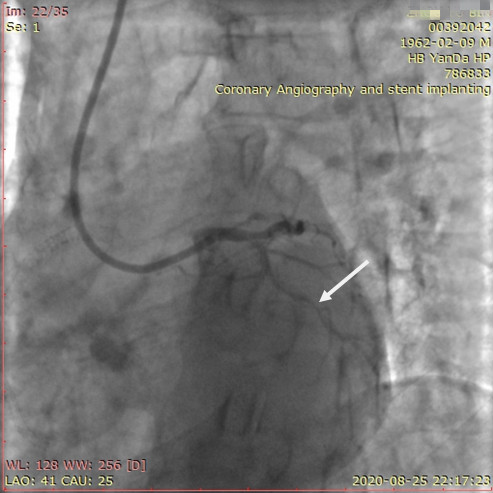

李先生足位術前影像

李先生足位術后影像